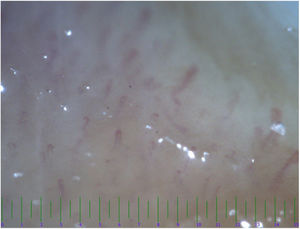

The nailfold capillaroscopy was conducted on both the KD and control groups. The abnormal capillaroscopic diameter was identified in 21 patients from KD group and four patients in the control group (Table 2). The most common abnormality in the evaluation of capillaries diameter was irregular dilatation (Fig. 1) seen in 11 (35.4%) KD patients and 4 (13.3%) in the control group. The normal capillary architecture distortions were commonly seen in KD group (n=8). On the other hand, there were no findings of architectural capillary abnormality in the control group (P=0.003). About half of KD patients had a reduction in capillary density (Fig. 2), while no similar abnormality was observed in the control group (P<0.001). There was no significant difference between KD patients and the control group in terms of morphology variations (P=0.4). Moreover, a positive correlation was observed between coronary involvement and abnormal capillaroscopic results (r=0.65, P<0.03).